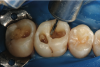

However, in the past decade, a new generation of low-shrinkage composites was developed specifically for bulk placement. These products’ advantages for placement relative to composites designed to be layered are radiographically apparent (Figure 1 and Figure 2); areas of porosity raise concerns about recurrent decay, and with a highly viscous composite, the chance of trapping air bubbles is significantly increased, compared to a dense, homogeneous void-free composite resin (Figure 2).2

Fig 1. Problems with incremental composite placement include potential voids and porosity when layering.

Figure 1